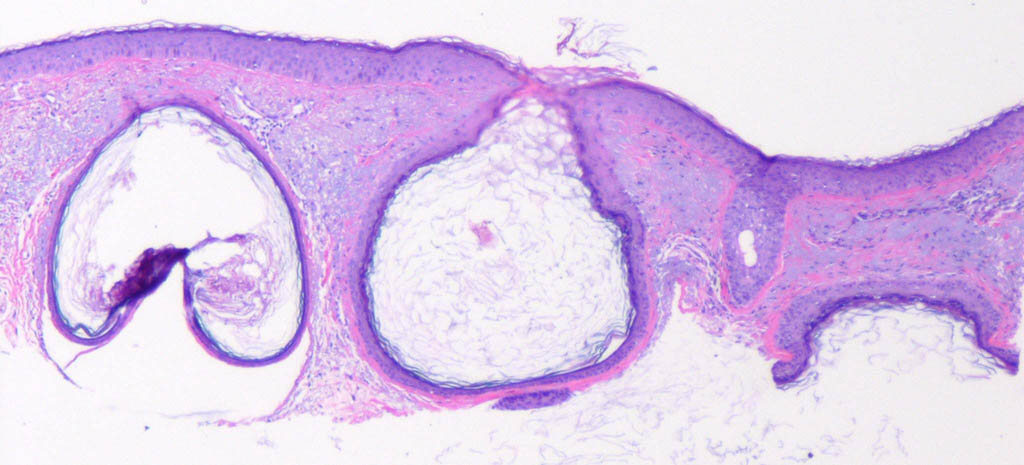

Comedonal acne = العد الزؤاني